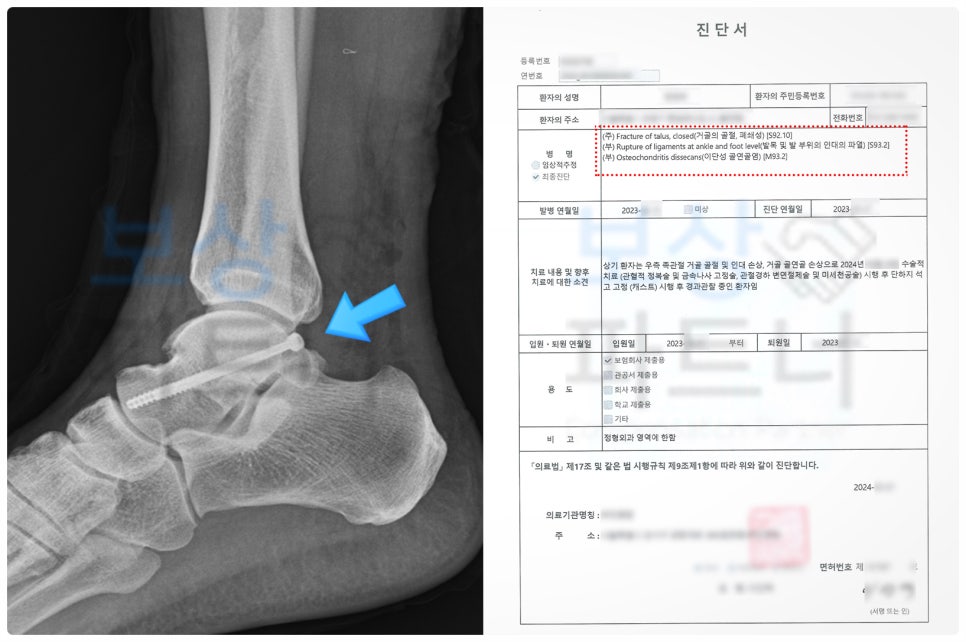

40대 후반이신 근로자께서는 현장 근무 중 계단에서 넘어지면서 발목 부상을 입으셨습니다.

재해자께서는 무사히 산재 승인을 받아 요양급여/ 휴업급여/ 장해급여 지급받으셨는데요.(총 4,200만 원) 비록 발목의 상태가 좋지 않았지만 운동 기능 장해는 인정받지 못하고, 일반 동통으로 장해등급 14급만 인정되었습니다.

이후 근재 신청을 위해 저희 사무실로 연락을 주셨고, 함께 청구를 진행하기로 결정하셨습니다. 그런데 산재에서 운동 기능장해를 인정받지 못했기 때문에 다소 불리한 상황이었는데요.

그럼에도 불구하고, 거골의 골연골염 손상 관련 의학적 기록과 유사 판례를 면밀히 검토하여 청구를 진행하였습니다.